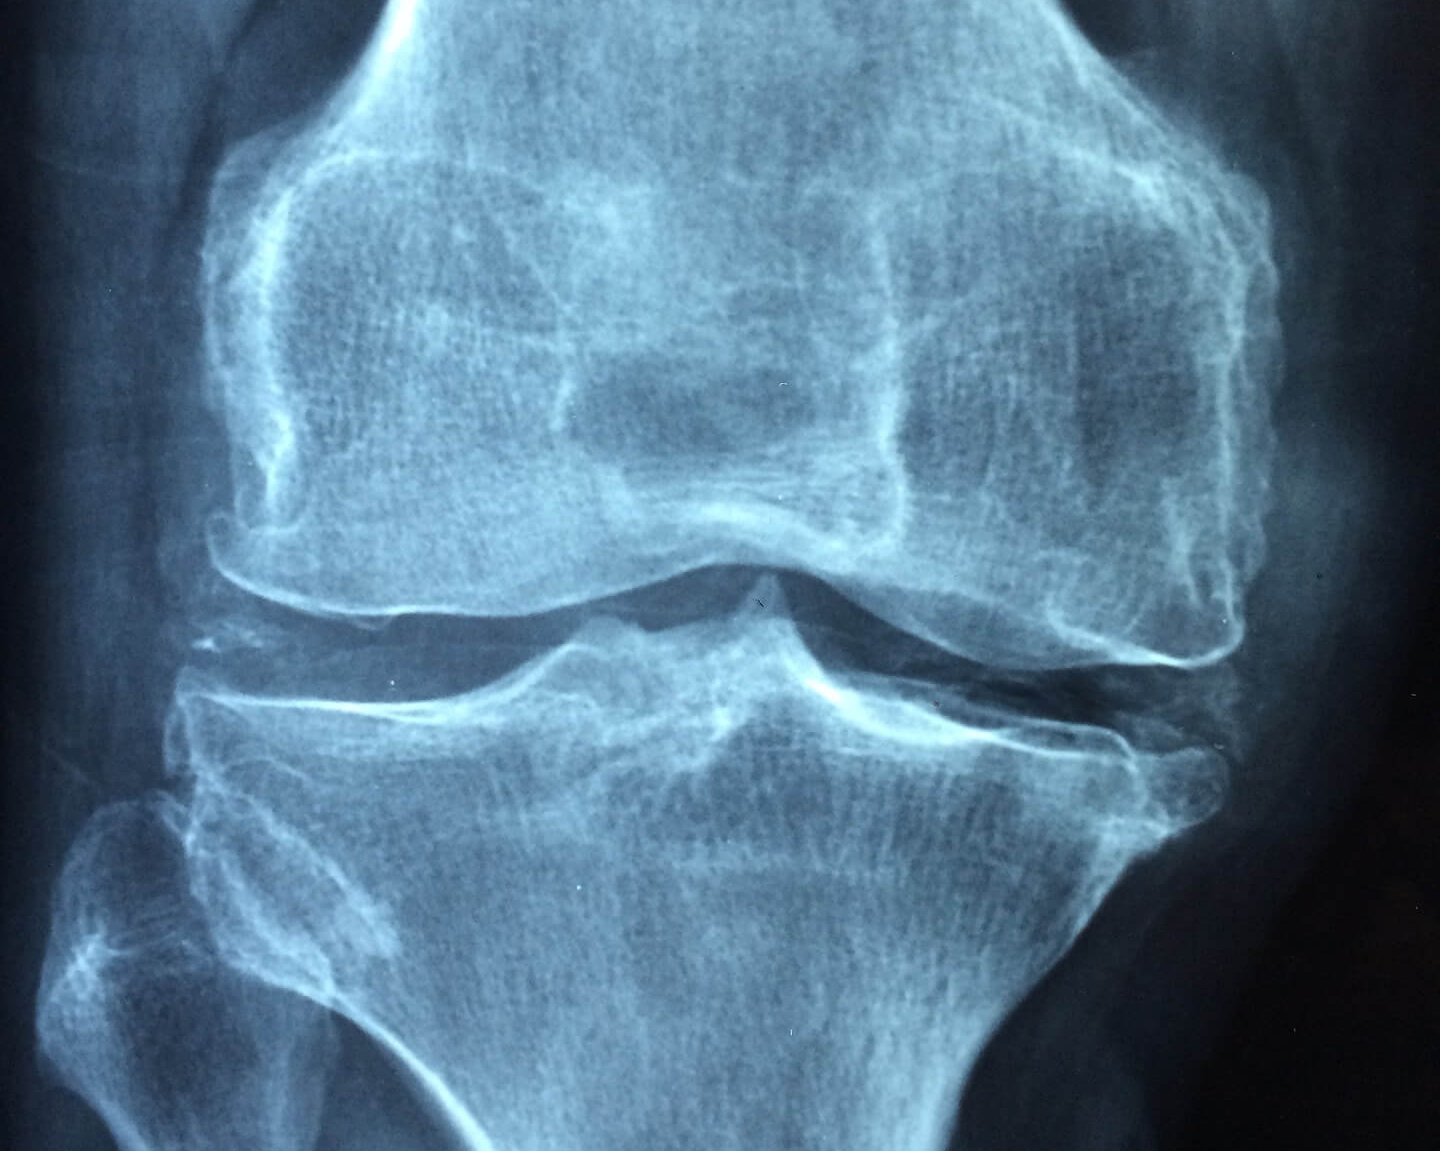

| 면역기능 이상이 원인이므로 나이에 상관없이 발생한다. 25~50세 사이의 나이 분포를 가진다. 어느날 갑자기 발생하며, 몸의 양쪽 에서 동시에 시작한다. 열이나 체중감소, 피로 등의 전신증상이 나타난다. 염증이 난다. 손가락 가운뎃마디에 생기고, 좌우대칭으로 생긴다. 움직이지 않아도 아픈 경우가 있다. 아침에 통증이 심하다. 혈액검사 및 X-선 검사로 진단

전체의 기능이 노화되면서 연골이 닿아서 생긴다. 40세 이후에 잘 발생한다. 여러 해 동안 서서히 진행되고, 몸의 어느 한 곳 관절에서 시작한다. 전신 증상은 없다. 염증이 없다. 손가락 끝 마디에 주로 먼저 생긴다 관절을 움직일 때 아프다 저녁 시간이나 잠잘 때 통증이 심해진다. X선 검사로 진단  |

다른 부위보다 더 위험한 엉덩이 관절 무릎관절인 퇴행성관절염은 염증에 의해 생기는 것이 아니라 연골이 닳아서 삐 와 뼈가 맞닿아 생긴 것이다. 따라서 체중이 실리는 관절부위에 질환이 생기면 다른 부위보다 문제가 더 심각해진다. 손에 생기는 퇴행성관절염은 손가락 끝 마디가 굵어지고 뼈가 튀어나와 보기는 좋지 않지만 그다지 큰 문제를 일으키지는 않는다.

체중이 실리는 엉덩이 관절(고관절)과 무릎관절은 퇴행성관절염이 쉽게 생긴다. 나이가 들면서 뼈를 지지해주는 근육이 줄어들면서 더 많은 하중을 관절이 지탱해야 하기 때문이다. 관절염이 심한 경우 걷는 것이 어렵거나 힘들어질 수 있으며, 문제가 생긴 관절에 물이 차면 걸을 때마다 뒤뚱거리게도 된다.